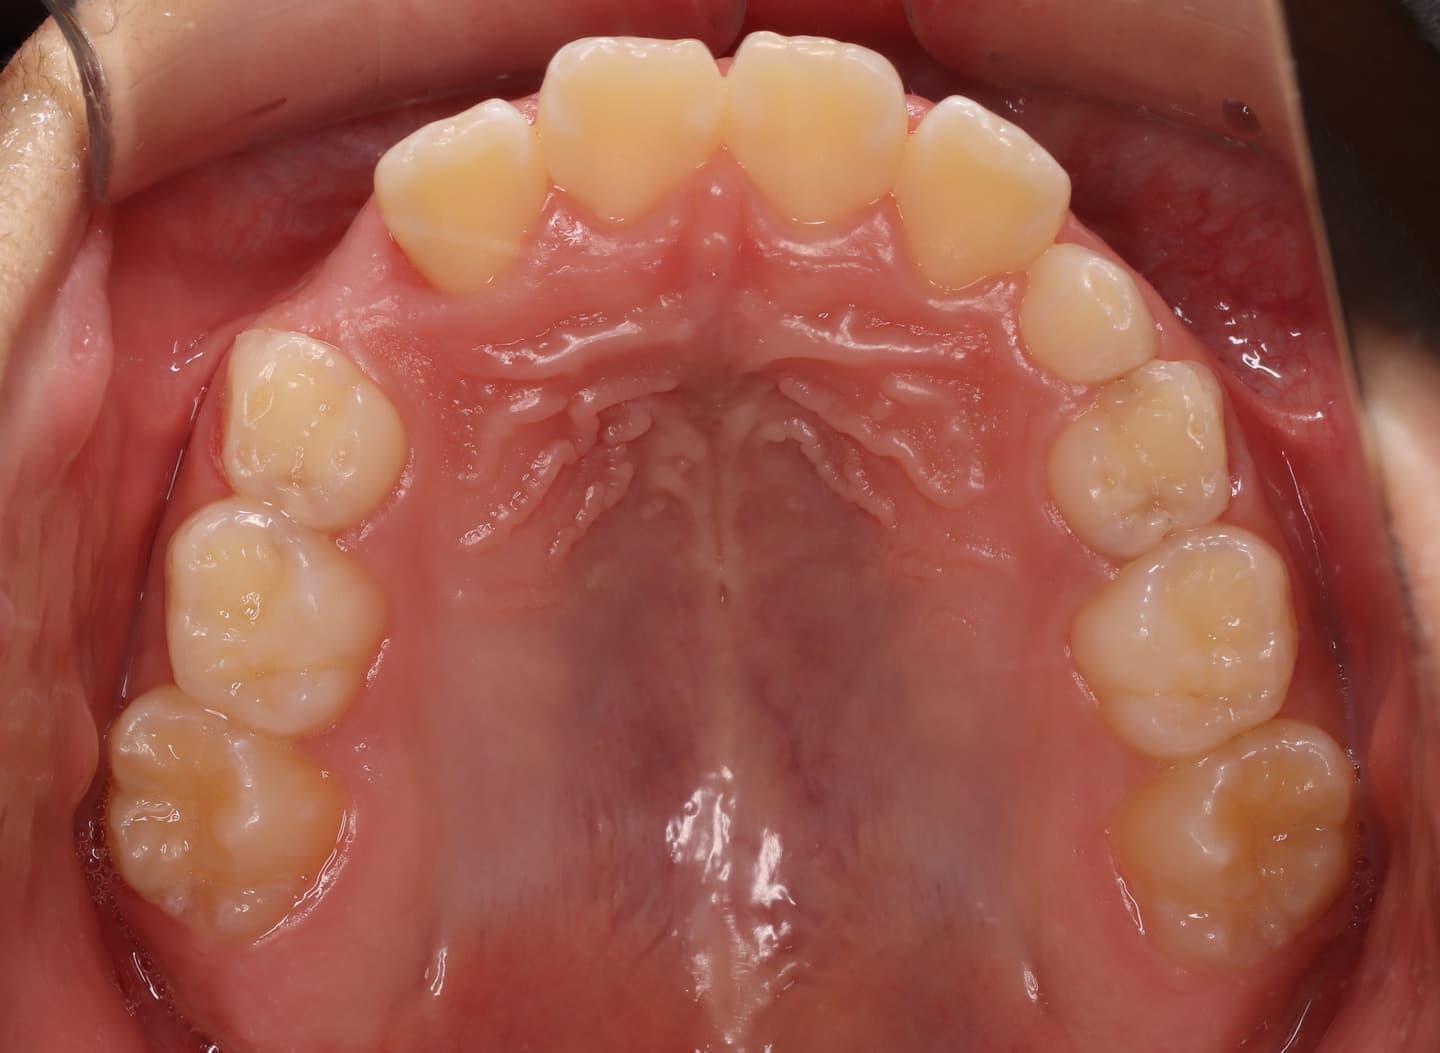

診断:初診時では右上3番の萌えるスペースがほとんどなく、顔と上顎と下顎の正中に対して、上顎前歯の正中が右にずれこんでいます。その影響で右上2番が右下乳歯Cと反対咬合になっています。放置すると、右上3番が埋伏歯になり、下顎の成長が左方向に流れるので、成長とともに顔面の非対称が増悪されることが予測されます。

右上乳犬歯が既に脱落しており、右上犬歯の萌出スペースがゼロになっています。